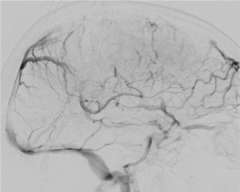

The blockage can result in brain swelling (edema), stroke, and/or bleeding in the brain (Figure 2).

Brain imaging studies such as MRI and CT are commonly used to demonstrate the clot in the cerebral venous sinuses. If necessary, catheter angiography is also performed to visualize the relatively small clots or when catheter based clot-removing treatment is needed (Figure 1).